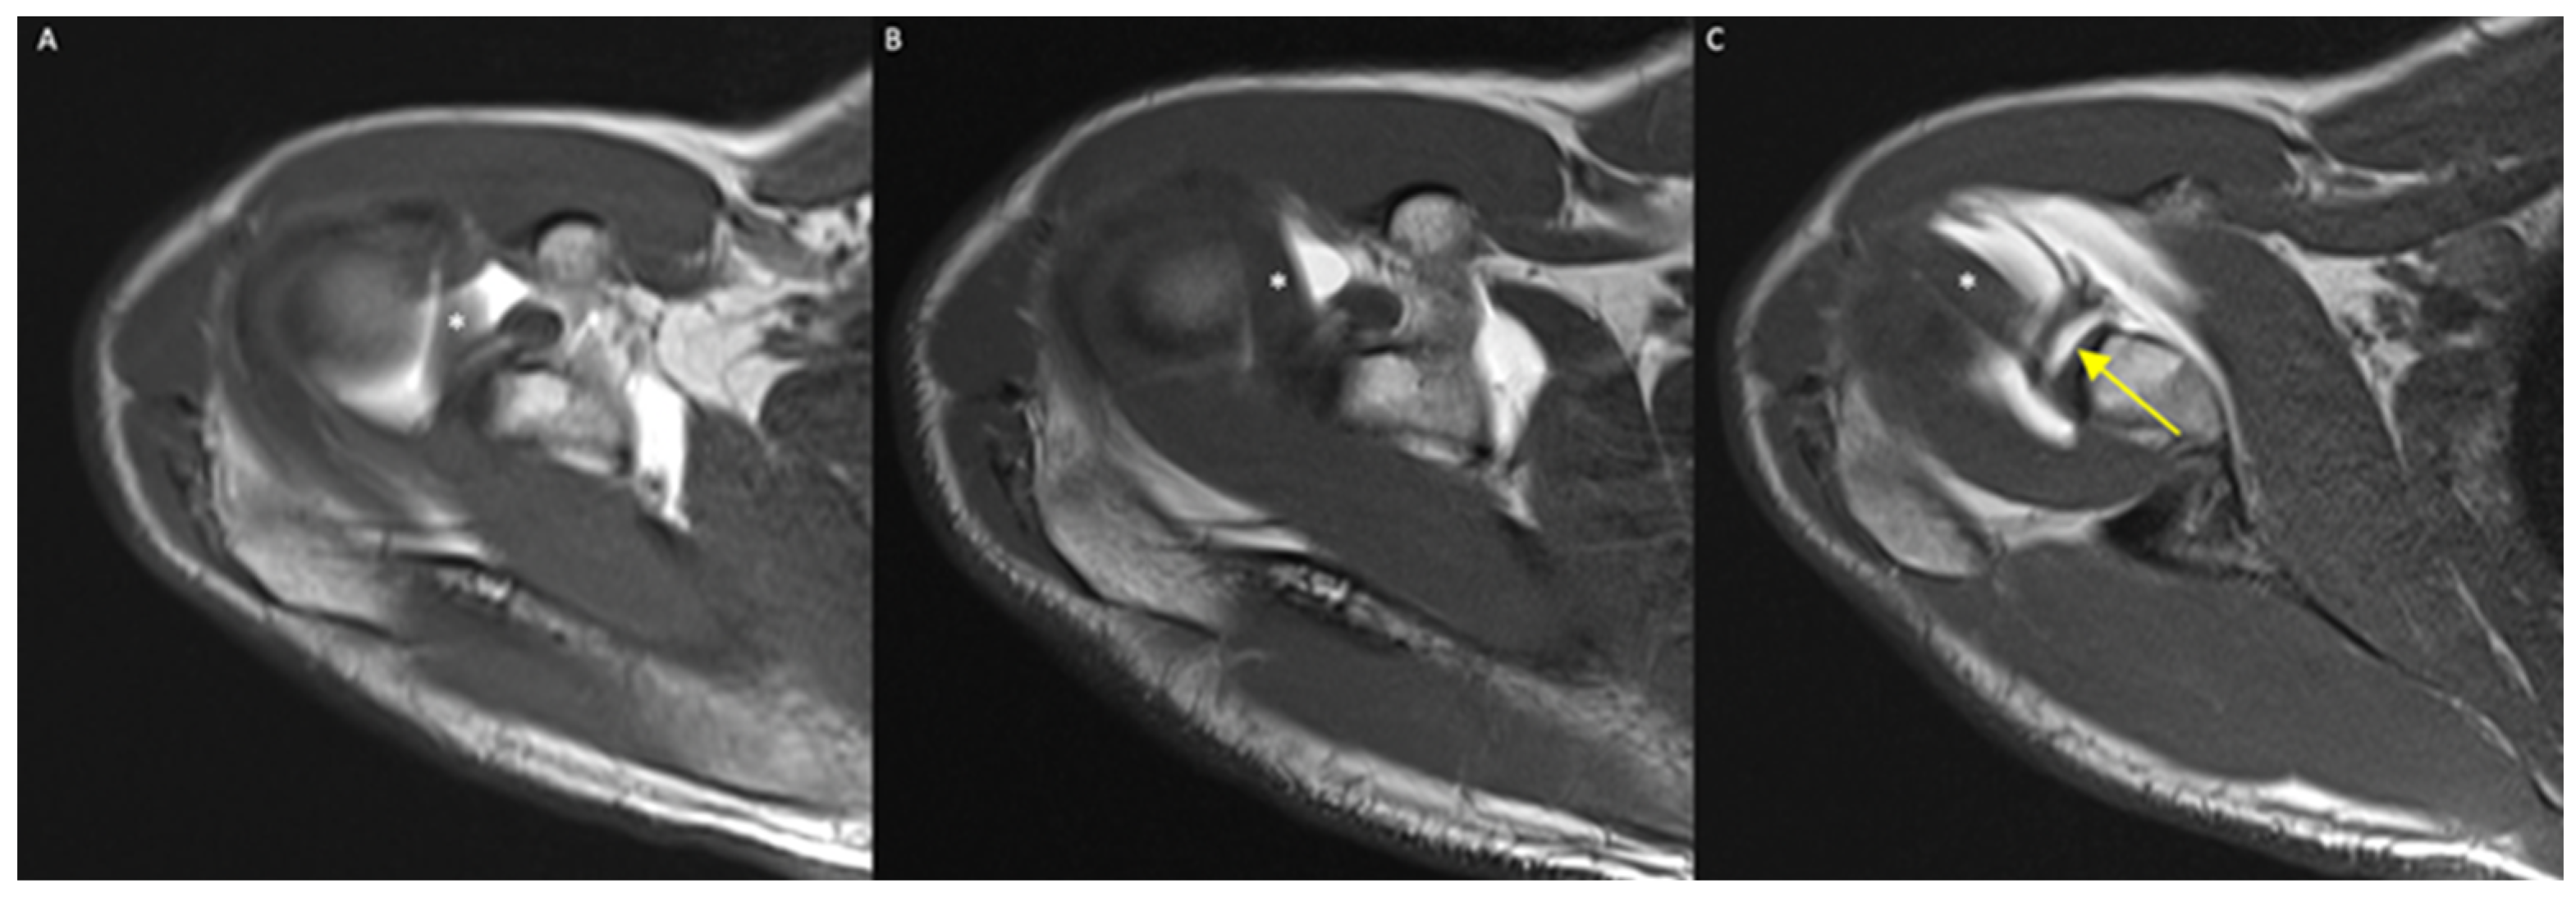

Rater 1’s diagnosis based on the MRA acquired in the ER or N positions differed in 19/130 cases (14.6%). In all such cases, the diagnosis was negative based on the MRA acquired in the N position but positive based on the images acquired in the ER position (Figure 6).

Figure 6.

(A–C) A 45-year-old male, axial T1-weighted images in IR (A), N (B), and ER (C) positions: only in the ER scan can a SLAP lesion be detected as a linear hyperintense contrast media infiltration within the bicipital–labrum complex (yellow arrow), representing a type II SLAP lesion. *: long head of the biceps tendon; (D–F) a 37-year-old male, axial T1-weighted images in N (D) and ER (E) positions, and coronal T1-w image in N position (F): a SLAP lesion is clear also in N standard position, but the ER of the humeral head increases the diastasis of the lesion (red arrow). Coronal image well demonstrates a bucket-handle tear of superior labrum (yellow arrow) with biceps tendon correctly attached to glenoid, expression of a type III SLAP lesion.